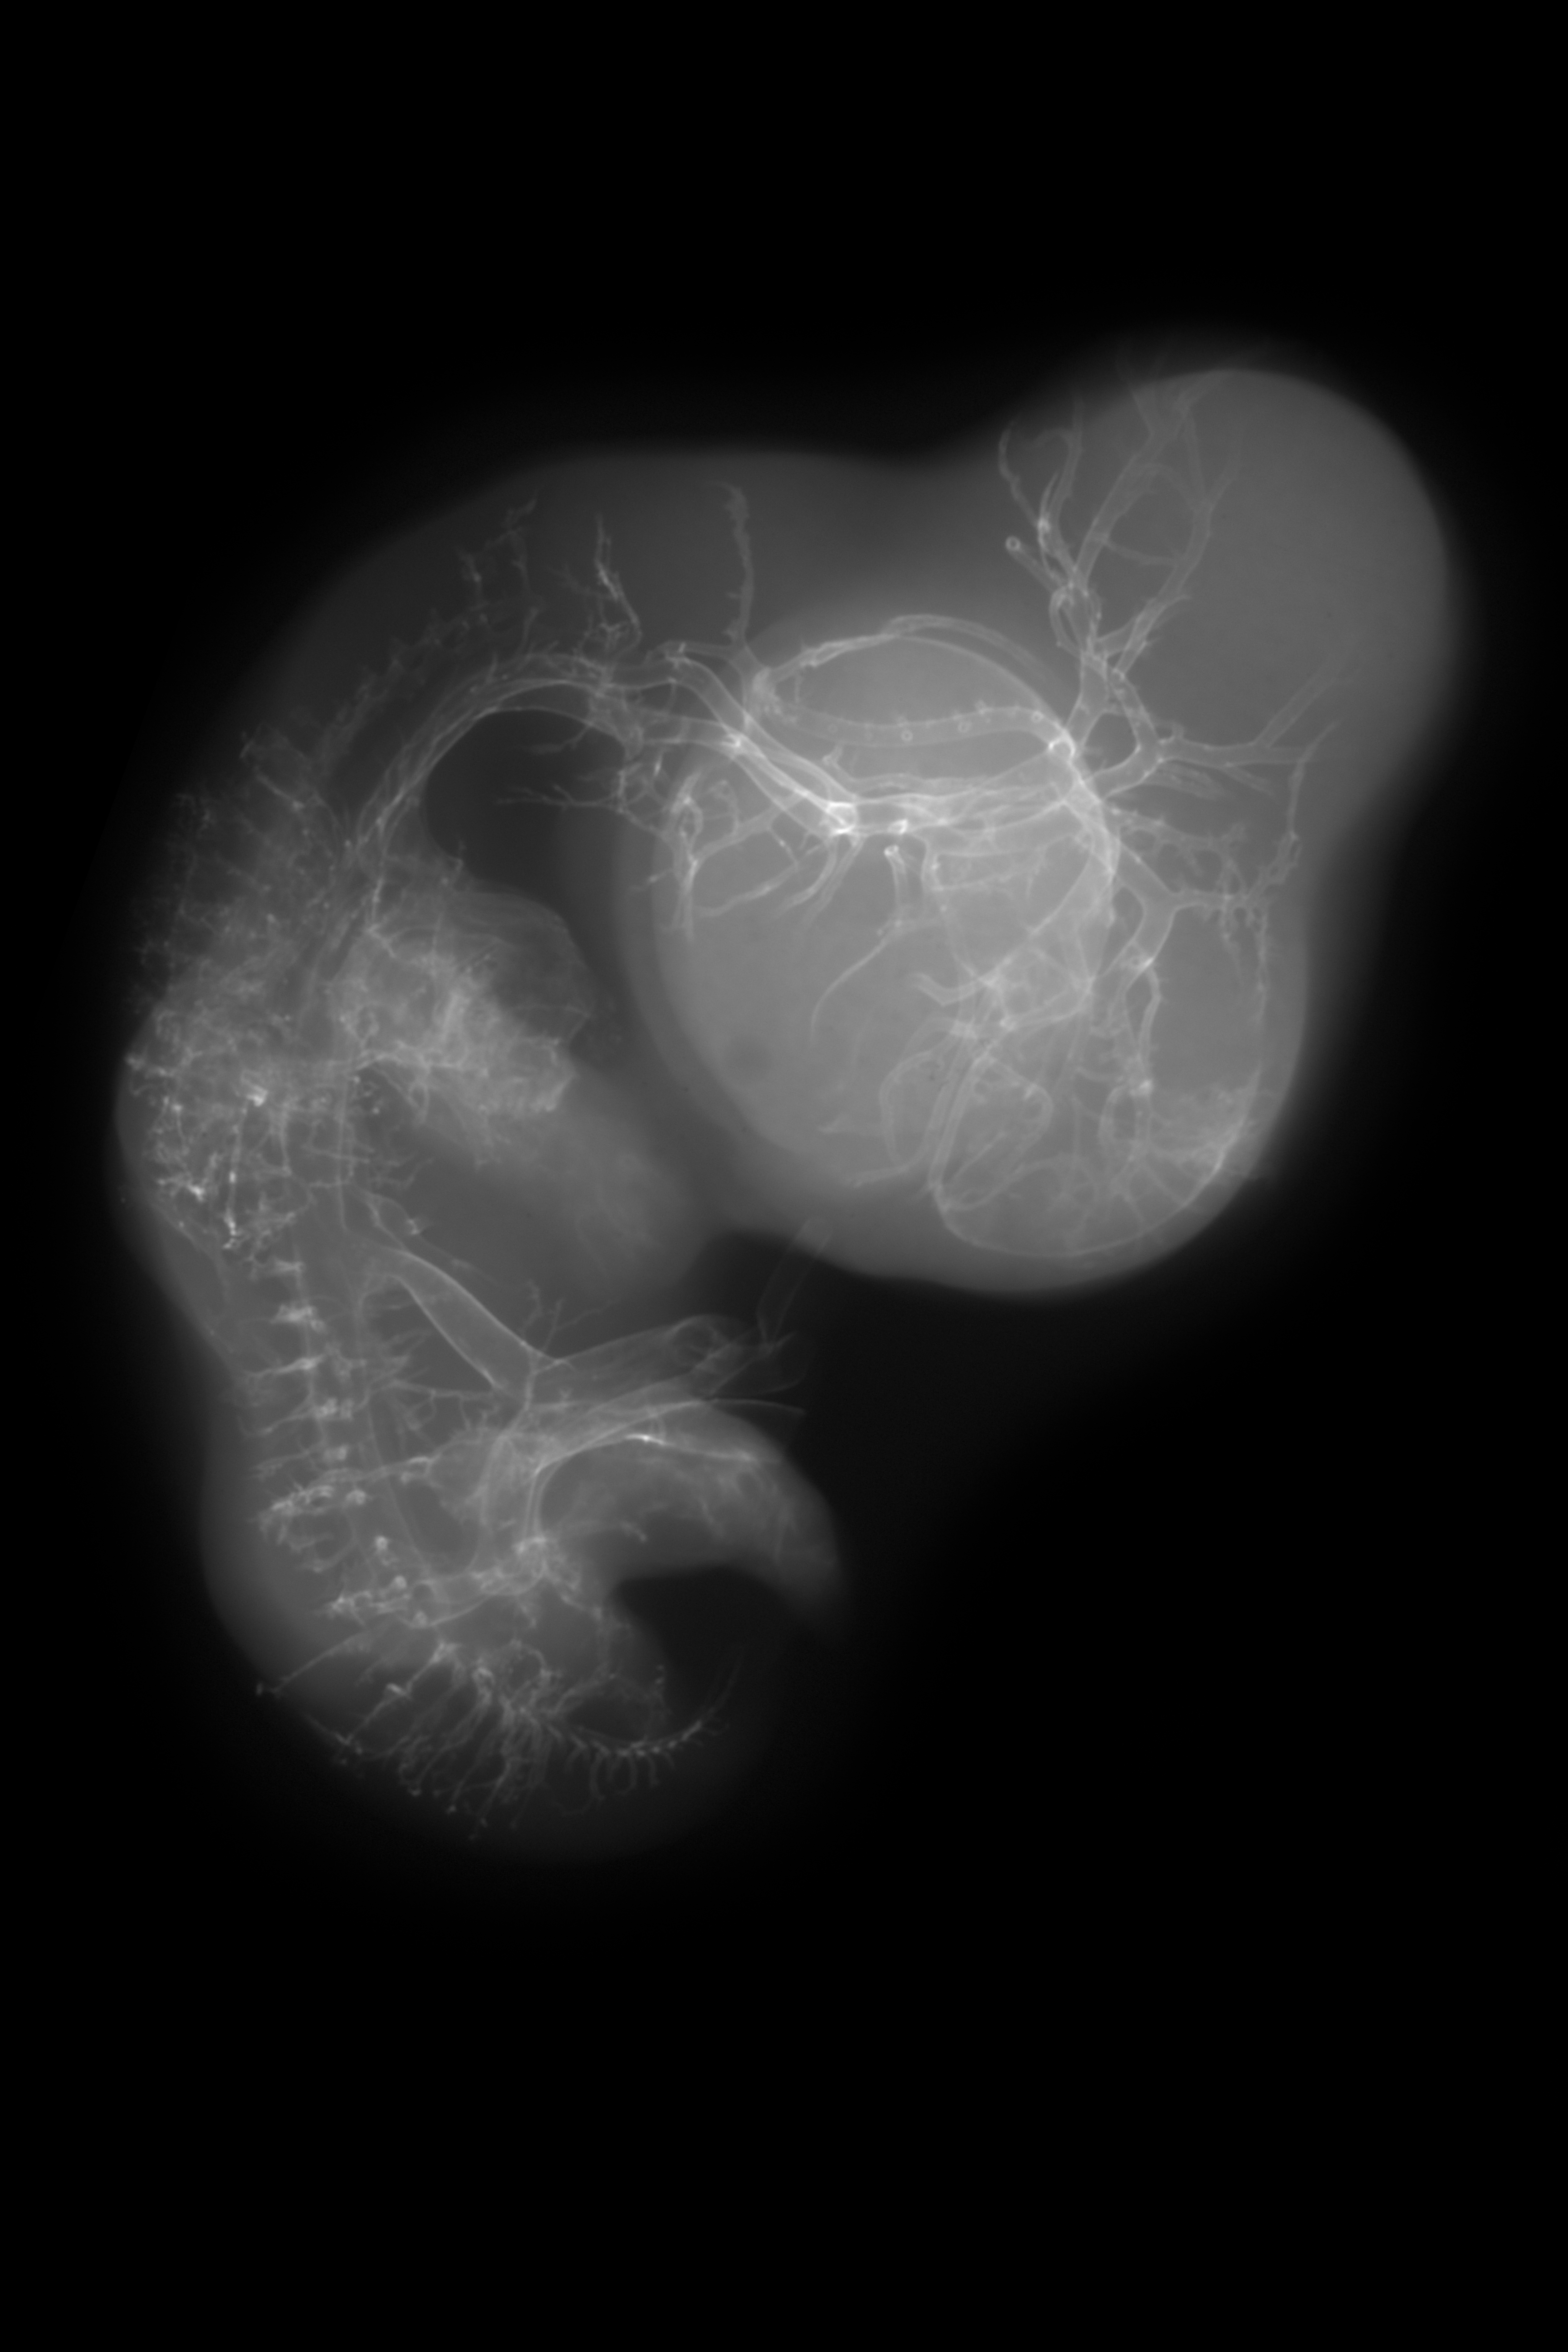

Chick Embryo Microangiography

Hamburger-Hamilton (HH) Stage 29 (approx. 6 - 6.5 days)

X-Ray Micrographs